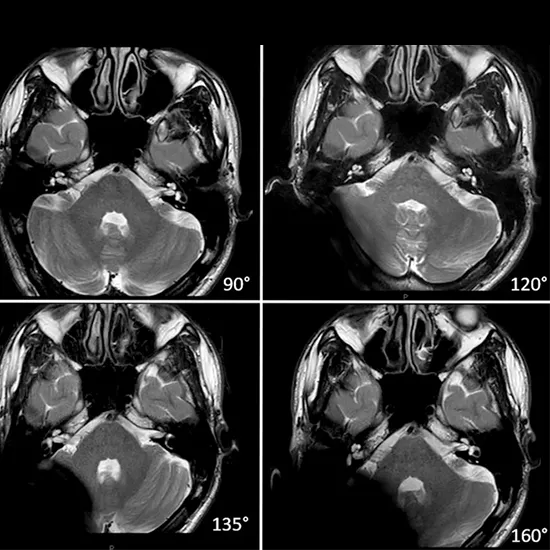

MRI (Magnetic Resonance Imaging) is an imaging procedure to make images of the body’s internal structures. MRI scanners use strong magnetic fields and radio waves to obtain the images. 3D Cochlear MRI obtains 3Dimensional images of the inner ear and hearing nerve.

Doctors recommend a 3D Cochlear MRI scan to evaluate the inner ear and hearing nerve. The scan gives your doctor confirmation if the cochlea has a normal shape or not.